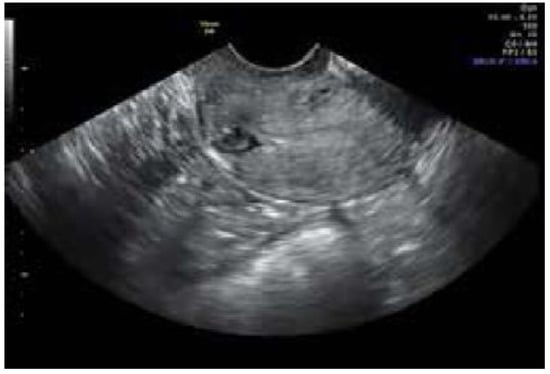

| Modality of Diagnosing Niche | Sonogram | 19 | 70% |

| Sonohysterogram | 3 | 11% | |

| MRI | 1 | 3.7% | |